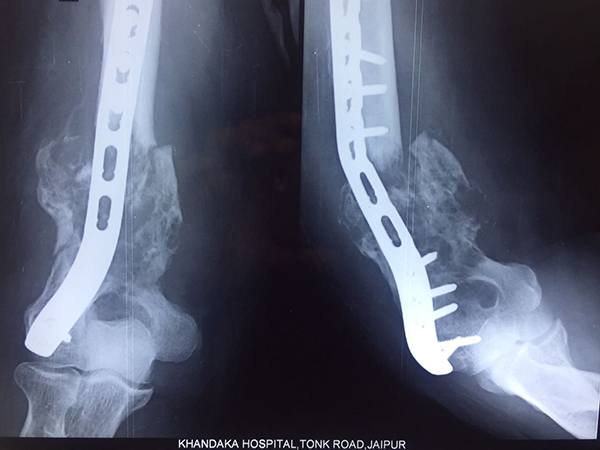

60yrs male k/c/o RCC with metastatic lesion at distal humerus operated by plate 2 yrs back, developed gross deformity at elbow joint, primary disease well controlled, single mets lesion.

Operated 3month before with wide excision and elbow reconstruction with endoprosthesis, post op 20-130 flexion and normal pronation supination without neurological deficits, pt is now able to drive scooter